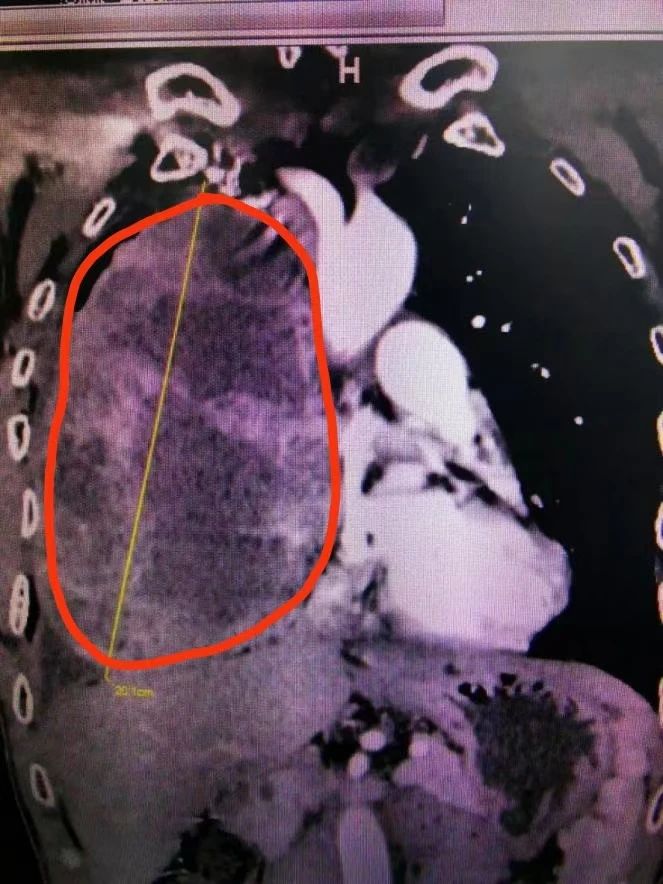

CT檢查(紅圈內為腫瘤)

實際上,李先生的情況確實比較棘手。鄧意平主治醫師表示,患者的胸部增強CT顯示前縱隔巨大腫瘤,因腫瘤巨大,腫瘤內滋養血管非常豐富,并累及右側胸腔大部,右肺受壓明顯;與心包、無名靜脈、上腔靜脈、右肺動脈等重要血管界限不清。

鄧意平主治醫師介紹,縱隔是一個解剖區域,位于兩肺之間,胸骨和胸椎為前后界。縱隔內原發腫瘤以良性多見,也有部分惡性。因其內有重要器官,原則上縱隔腫瘤一經發現,建議手術治療,對于直徑大于10厘米的腫瘤被稱之為巨大縱隔腫瘤,該患者的腫瘤達20多厘米的情況實屬罕見。